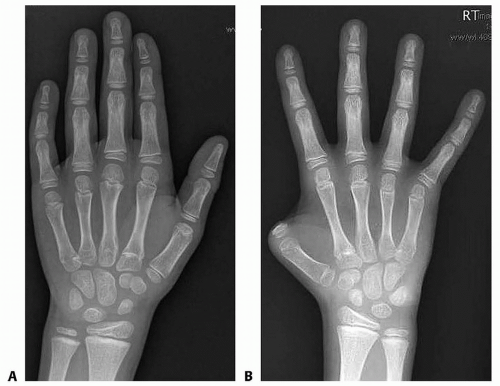

Review preoperative radiographs of the recipient site to prepare for bone fixation and length requirement of donor toe (FIG 4).

FIG 4 • Preoperative radiograph of recipient hand. Amputation level is at the proximal phalanx base. Contralateral radiographs help estimate defect length.

The length of the transferred toe should be based on the length of the contralateral uninjured thumb (see FIG 4).